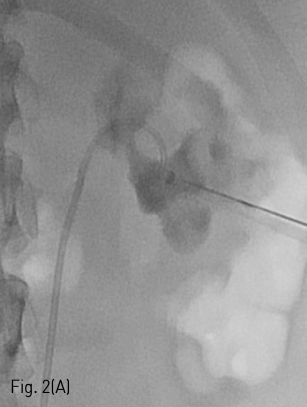

Fig 2A

(A-B) Chiba needle was advanced under fluoroscopic guidance until entrance into the renal pelvis.

환자는 왼쪽 신장의 isolated calyx에는 8.5Fr. drainage catheter가 insertion 되어 있고 left renal pelvis에는 double J stent가 insertion 되어 있는 상태로 prone position을 취하였다. 기존의 drainage catheter에 0.035inch 유도 철사(Terumo, Tokyo, Japan)를 insertion 하고 catheter는 제거한 후 8Fr. Sheath(Boson, Shrewsbury, USA)를 삽입하였다. 조영제(Visipaque, GE healthcare, Chicago, USA)를 주사하여 tubogram을 시행하였고 isolated calyx 와 콩팥깔때기와의 연결성은 없었다. (Fig.1B) 초음파 유도 하에 21G 천자바늘(Cook, Bloomington, USA)로 isolated calyx를 천자하고 X선 투시하에 천자바늘을 콩팥깔때기에 insertion 되어 있는 double J catheter를 향해 진입시켰다. (Fig. 2A, B) 천자바늘의 속심을 제거한 후 X선 투시하에 조영제를 주사하여 isolated calyx를 지나 콩팥깔때기가 천자된 것을 확인하고 0.018inch 유도 철사(A & A, Gyeonggi, Korea)를 넣었다. (Fig. 2C) 이후 천자바늘을 제거하고 단일 막대 접근 장치(yellow sheath; A & A, Gyeonggi, Korea)를 이용하여 접근로를 확보했다. 유도 철사와 metal stiffening inner cannula를 제거하고 0.035inch 유도철사(Terumo, Tokyo, Japan)를 넣고 6mm x 4cm balloon(Boson, Shrewsbury, USA)을 이용하여 isolated calyx와 콩팥깔때기 간 neoinfundibulum 을 재건하였다. (Fig. 2D) 삽입되어 있는 유도 철사를 통해 isolated calyx, neoinfundibulum 그리고 콩팥깔때기를 차례로 통과하도록 10.2Fr. nephrostomy catheter(Cook, Bloomington, USA)를 위치시켰다. (Fig. 2E) 4일 후 기존의 10.2Fr PCN catheter insertion site를 통하여 10Fr sheath(Terumo, Tokyo, Japan)를 insertion 한 뒤 0.035inch 유도철사(Terumo, Tokyo, Japan)를 방광까지 진입시킨 뒤, 26cm 7Fr double J stent(Boson, Shrewsbury, USA)의 원위부는 방광에 위치시키고 근위부는 isolated calyx에 위치시켰다.(Fig. 3) 이후 isolated calyx로의 접근로에는 10.2Fr. nephrostomy catheter(Cook, Bloomington, USA)를 삽입하고 시술을 종료했다.